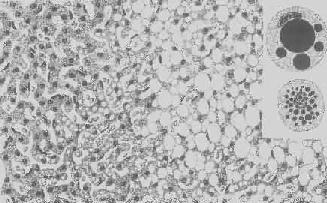

图1-17 肝细胞气球样变 病毒性肝炎时,肝细胞明显肿胀,胞浆疏松呈气球样 形态学:轻度肝脂肪变性时,肝肉眼观可无明显改变,或仅轻微黄染。如脂仿变性比较显著和广泛,则肝增大,色变黄,触之质如泥块并有油腻感。镜下,肝细胞内的脂肪空泡较小,起初多见于核的周围,以后变大,较密集散布于整个胞浆中,严重时可融合为一个大空泡,将细胞核挤向胞膜下,状似脂肪细胞(图1-18)。脂肪变性在肝小叶中的分布与其病因有一定的关系,例如肝淤血时,小叶中央区缺氧较重,故脂肪变性首先在此处发生。但长期淤血后,小叶中央区的肝细胞大多萎缩、变性或消失,于是小叶周边区肝细胞也因缺氧而发生脂肪变性。磷中毒时,肝细胞脂肪变性则主要发生于小叶周边区,这可能是由于此区肝细胞对磷中毒更为敏感的缘故。

图1-18 肝细胞脂肪变性 肝细胞胞浆内出现大小不等的脂肪空泡;右上角为饿酸染色的脂肪细胞, 脂滴染成黑色 (2)心肌脂肪变性:心肌在正常情况下可含有少数脂滴,脂肪变性时脂滴明显增多。镜下,脂肪空泡较细小,呈串珠状成排排列,主要位于肌纤维Z带附近和线粒体分布区。常为贫血和中毒的结果。在严重贫血时,可见心膜下尤其是乳头肌处出现成排的黄色条纹,与正常心肌的暗红色相间排列,状若虎皮斑纹,故有“虎斑心”之称。严重感染、白喉外毒素以及其他毒物(如磷、砷、氯仿等)也能引起心肌的弥漫性脂肪变。肉眼观,心肌均匀变浊,略呈黄白色。但通常心功能并不受明显影响。显著的心肌脂肪变性如今并不常见。 (3)肾脂肪变性;在严重贫血、缺氧和中毒过程中,或肾小球毛细血管通透性升高时,肾小管特别是近曲小管的上皮细胞可吸收漏出的脂蛋白而导致脂肪变性。脂滴起初多位于细胞基底部。肉眼观,肾稍肿大,切面上可见皮质增厚,略呈浅黄色。 2.玻璃样变性 又称透明变性(hyaline degeneration),为十分常见的变性,主要见于结缔组织、血管壁,有时也可见于细胞内。 1.结缔组织玻璃样变:常见于纤维瘢痕组织、纤维化的肾小球,以及动脉粥样硬化的纤维性瘢块等。此时纤维细胞明显变少,胶原纤维增粗并互相融合成为梁状、带状或片状的半透明均质,失去纤维性结构(图1-19)。质地坚韧,缺乏弹性。玻璃样变的发生机制尚不甚清楚,有人认为在纤维瘢痕老化过程中,原胶原蛋白分子的交联增多,胶原原纤维也互相融合,其间并有较多的糖蛋白积聚,形成所谓玻璃样物质;也有人认为可能由于缺氧、炎症等原因,造成局部pH升高或温度升高,致使原胶原蛋白分子变性成明胶并互相融合所致。 2.血管壁玻璃样变:这种改变常见于高血压病时的肾、脑、脾及视网膜的细动脉。此时,可能是由于细动脉的持续性痉挛,使内膜通透性增高,血浆蛋白得以渗入内膜,在内皮细胞下凝固成无结构的均匀红染物质。此外,内膜下的基底膜样物质增多。这些改变使细动脉的管壁增厚、变硬,管腔变狭,甚至闭塞(图1-20),此即细动脉硬化症(arteri-olosclerosis),可引起肾及脑的缺血。 3.细胞内玻璃样变:亦称为细胞内玻璃样小滴变性。这种情况常见于肾小球肾炎或其他疾病而伴有明显蛋白尿时。此时肾近曲小管上皮细胞胞浆内可出现许多大小不等的圆形红染小滴(图1-21),这是血浆蛋白经肾小球滤出而又被肾小管上皮细胞吞饮的结果,并在胞浆内融合成玻璃样小滴,以后可被溶酶体所消化。此外,在酒精中毒时,肝细胞核周胞浆内亦可出现不甚规则的红染玻璃样物质。电镜下,这种物质由密集的细丝构成,据认为可能是细胞骨架中含角蛋白成分改变的结果,并被称为Mallory小体。